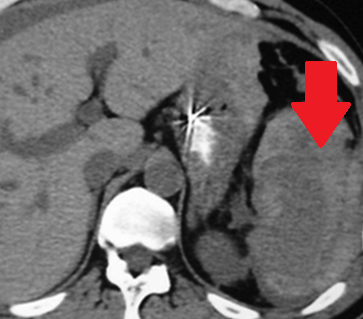

Αυτόματη ρήξη/αιμορραγία νεφρού — νεφροκυτταρικό καρκίνωμα (Ευγενική παραχώρηση Dr. V. Penopoulos)